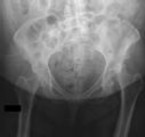

A 13-year-old obese boy presents with non-traumatic knee pain and is noted to have an obligate external rotation of his hip when it is passively flexed. Radiographs confirm the diagnosis. He is unable to bear weight on the affected extremity. What is the primary complication associated with this presentation compared to a patient who is able to bear weight?

Correct Answer: Avascular necrosis (AVN) of the femoral head

Explanation:

The patient has an unstable slipped capital femoral epiphysis (SCFE), defined by Loder criteria as the inability to bear weight even with crutches. Unstable SCFE has a significantly higher rate of avascular necrosis (up to nearly 50% in some series) compared to stable SCFE (which has an AVN rate near 0%). Both stable and unstable SCFEs can lead to impingement or contralateral slips, but AVN is the critical distinguishing risk factor of an unstable slip.